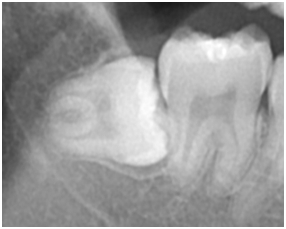

それでは早速ですが、レントゲン画像を用いて説明していこうと思います!

それぞれの画像の左側の歯が、親知らずになります。1枚目の親知らずは、隣の歯(第二大臼歯)と同じレベルの高さまで萌出しています。2枚目の親知らずは、2枚目と同様に横向きで隣の歯に衝突していますが、やや浅い位置で埋まっている状態です。1枚目の親知らずのように、正常に萌出できれば特に問題はないのですが、現代人は顎が小さくなり、奥のスペースが不足しているため、最後に生える親知らずが、2枚目の画像のように隣の歯に衝突し、斜めや横向きに埋まったままになるケースも少なくありません。先天的に親知らずが存在しないケースも含めると、おおよそ4人に1人は、親知らずが生えてこないというふうにも言われています。